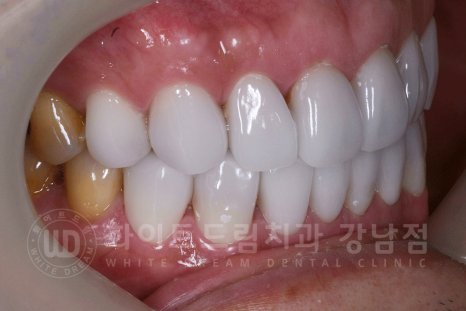

▲ 강남역 인근 치과, 강남 화이트드림치과 전치부 라미네이트 후

환자분은 14 - 24 / 34 - 44까지의 총 8개의 치아를 라미네이트로 진행하셨습니다.

동일 인물이며, 동일 환경에서 촬영되었습니다. / 강남역 인근 치과

(치료 기간 : 23.12.11 - 23.12.18)

오늘 알려드린 사례자 분과 비슷한 정도의 변색이라면 간단하게 라미네이트로 드라마틱한 개선이 가능하답니다. ^^

저희 강남화이트드림치과의 정수윤 대표원장님이 직접 진행하신 케이스이며

40년 동안 어두운 치아로 너무 스트레스였어요.

제일 밝은색의 치아로 만들어 주세요!

라는 환자분의 요청에 맞추어 상담 후 제일 밝은 색상의 보철로 제작을 하였습니다.

치아 색상만 바뀌었는데도 피부나 인상이 환해진 것을 확인할 수 있습니다. ^^